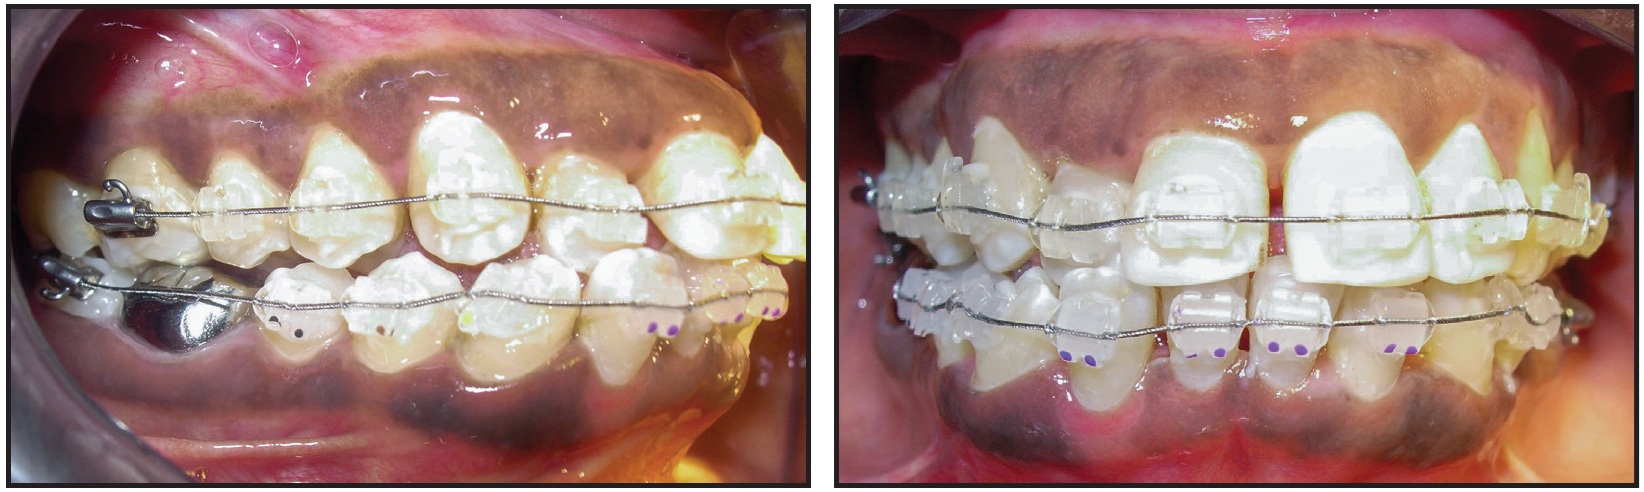

Six months later, a three-month phase of orthodontic finishing was carried out to close the residual spaces in the lower arch. A continuous elastomeric chain was placed from the lower right second molar to the lower left first molar, initially bypassing the right lateral incisor to minimize the forces on this tooth. After correction of the anterior crossbite and closure of residual spaces, the bite planes and fixed appliances were removed (Fig. 7). A normal overbite of about 2mm ensured stability of the anterior crossbite correction.

Fig. 7 After three months of orthodontic finishing, following six months of periodontal treatment and healing.

During a total 14 months of treatment, the metal crown on the lower right first molar collapsed due to the heavier occlusal forces from the bite plane on the opposing upper molar. A new metal crown was placed at the end of treatment (Fig. 8).

Fig. 8 Patient after 14 months of treatment.

This multidisciplinary approach allowed the preservation of a compromised natural tooth while improving esthetics and function.